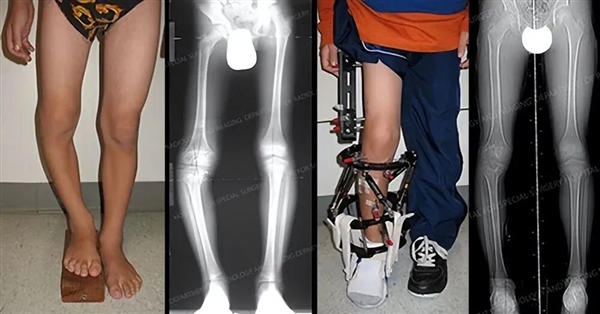

腿部畸形矫正案例

选择做腿部缩短术的人,大多选择切除部分股骨,就是我们常说的大腿骨。

切除一截股骨后,再植入金属设备将两截断骨接上固定住,等切开处骨头愈合再将金属取出,腿外部不需要用其他设备固定。

诊所声称,这么一操作,身高可以降低5cm以上。除了股骨,胫骨也可以切,大腿最多可缩短 5.5 厘米,小腿最多可缩短 3 厘米。

在过去,只有腿部有问题(例如畸形和长短腿)影响正常生活的人,才会冒险选择这样的治疗方式,而如今,却成了人们改变外观的一种手段。